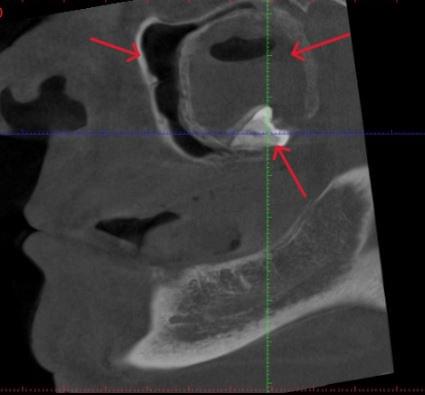

КПКТ (конусно-променева комп’ютерна томографія) — це 3D-знімок високої роздільної здатності. На відміну від звичайного рентгену, КТ показує:

Діагностика гайморових пазух за допомогою КТ

У сучасній медицині КТ придаткових пазух носа (або КТ синусів) — це «золотий стандарт»

діагностики для ЛОР-лікарів та щелепно-лицевих хірургів. Звичайний рентген часто не

показує повну картину, а МРТ не завжди доступний і дорожчий. Комп’ютерна томографія дає

детальну 3D-модель усіх пазух (гайморових, лобних, клиновидних та решітчастого

лабіринту) за 10 секунд і з мінімальною дозою опромінення.